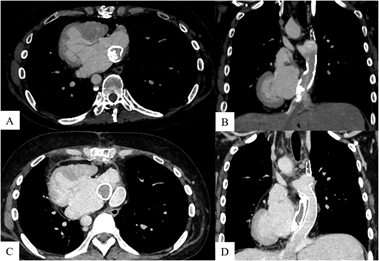

Contrast-enhanced computed tomography (CT) revealed 65% stenosis due to calcification within the intra-atrial conduit (Fig. 1). Blood test results were not indicative of Fontan-associated liver disease; on the other hand, the patient’s brain natriuretic peptide concentration had increased from 72 pg/mL (5 years ago) to 216 pg/mL. The patient was considered a candidate for surgical intervention because of increasing calcification and detectable symptoms.